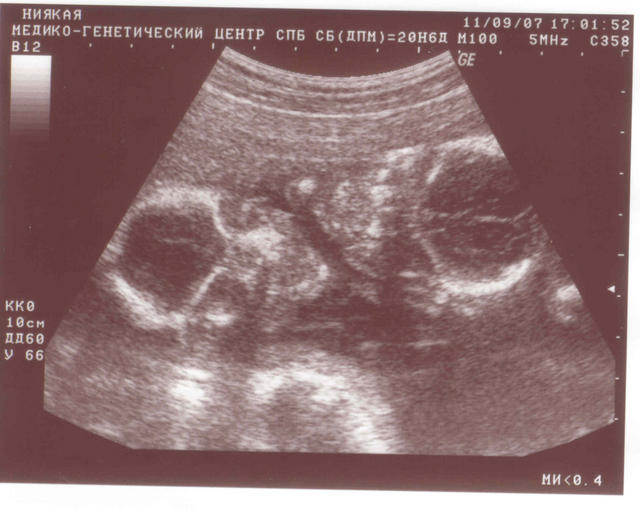

С пузиком нет, а мальчуганы есть)

Изображения